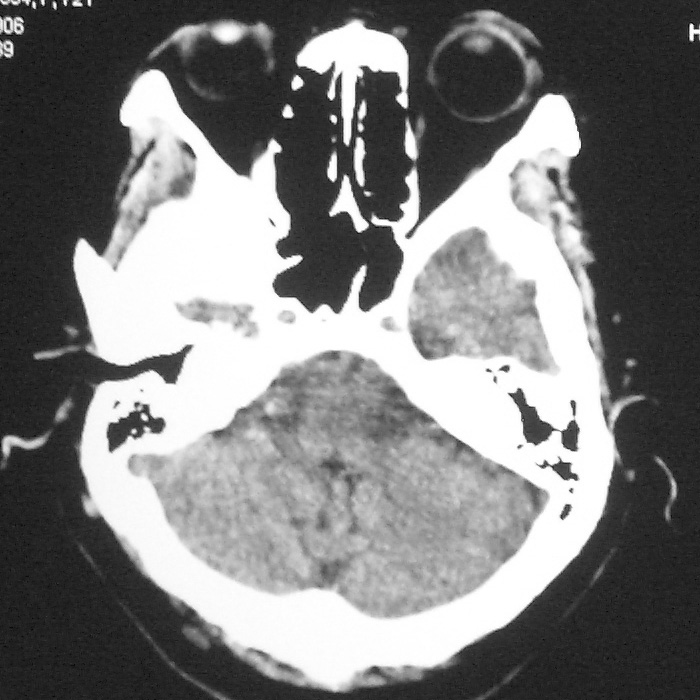

f,70y,口角歪斜、流涎、吐词不清三天

左侧大脑基底节区点状低密度影,边缘清楚,左侧腔梗或软化灶,没什么问题啊?

左侧基底节区示点状低密度灶,边界清楚,密度均匀,余所示无著变。

意见:腔隙性脑梗塞(左基底节区)

各位老师,报告这么写可以吗?右侧我没有看出来。